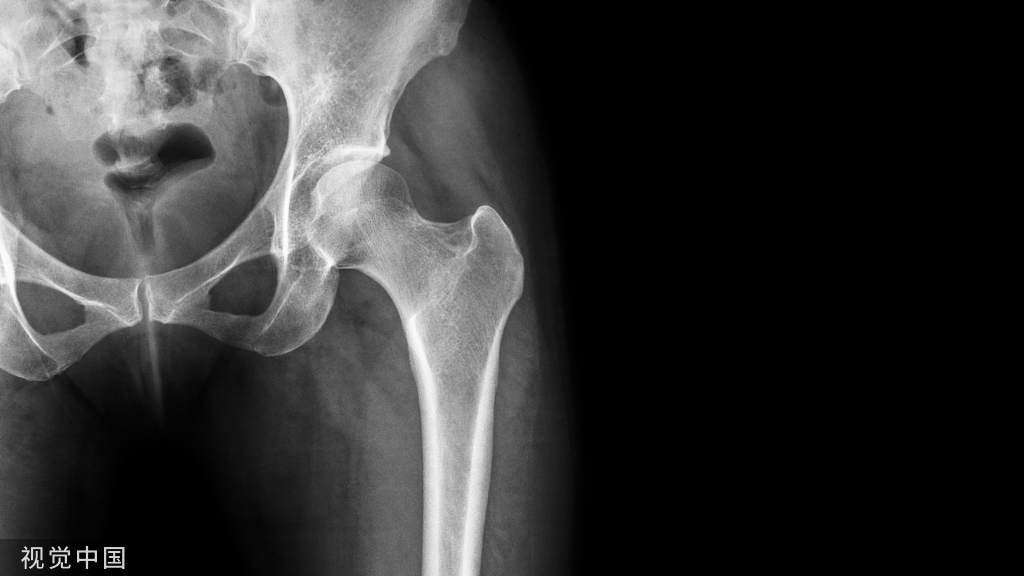

1.骨折时损伤有一定的报道提示骨盆骨折时该血管断裂损伤,尤其是在耻骨支外4-6cm处骨折时需要注意。